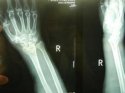

上一期91视频污污污讲诉了患桡骨远端骨折的原因及其注意事项, 91视频下载免费仪品牌 91视频污污污继续为您讲述桡骨骨折后如何更好的恢复。 1、俗话说伤筋动骨一百天,有钢板的在1年内每月到医院复

桡骨是人体前臂双骨之一,位于前臂外侧,大拇指一侧,分为一体和两端。是前臂长骨之一;蛙、蟾蜍等动物的桡骨与尺骨愈合成桡尺骨。 91视频下载免费仪厂家 91视频污污污为您讲述桡骨引起的